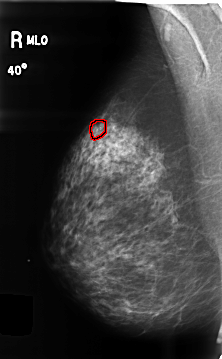

B_3459_1.RIGHT_MLO

RIGHT_MLO LINES 4656 PIXELS_PER_LINE 2880 BITS_PER_PIXEL 12 RESOLUTION 50 OVERLAY

FILE: B_3459_1.RIGHT_MLO.OVERLAY

TOTAL_ABNORMALITIES 1

ABNORMALITY 1

LESION_TYPE CALCIFICATION TYPE PLEOMORPHIC DISTRIBUTION CLUSTERED

ASSESSMENT 4

SUBTLETY 4

PATHOLOGY BENIGN

TOTAL_OUTLINES 1